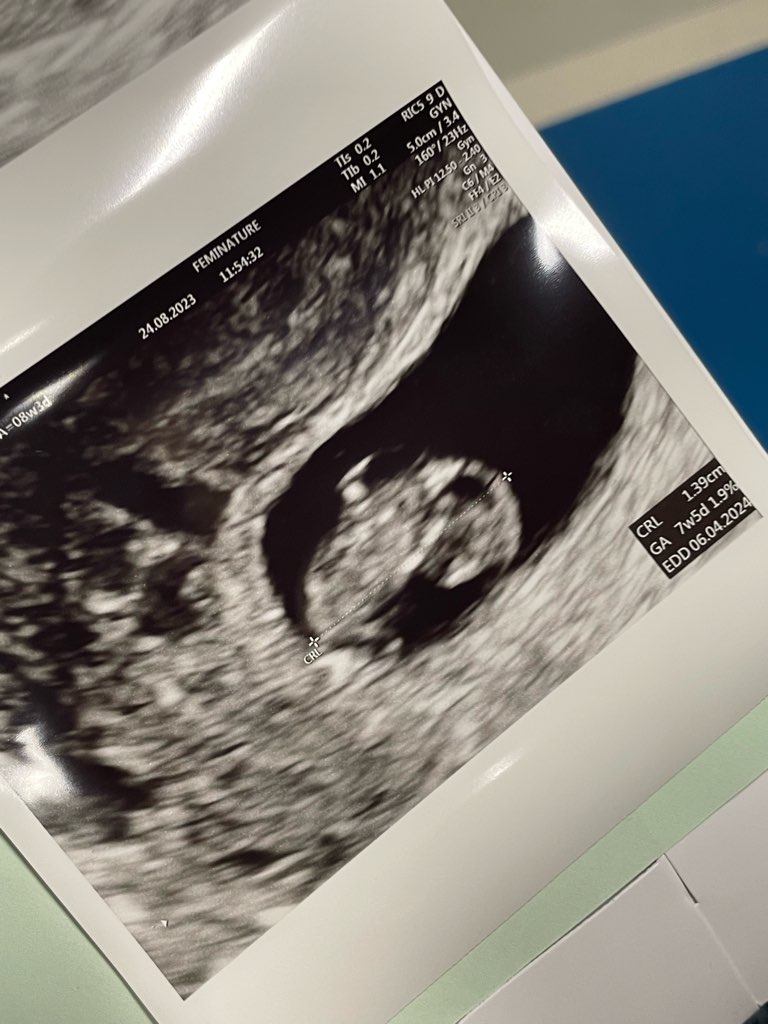

u mnie też PTP to 06.04Ja już po wizycie, jest jasiek fasol i jest serduszko.

Wychodzi 7+5 a z terminu OM 7+4.

Według dzisiejszego usg termin 6 kwiecień, 2 tyg temu na usg u innego lekarza był 8 kwiecień. Wszystko ok.

Za 2 tygodnie następna wizyta.